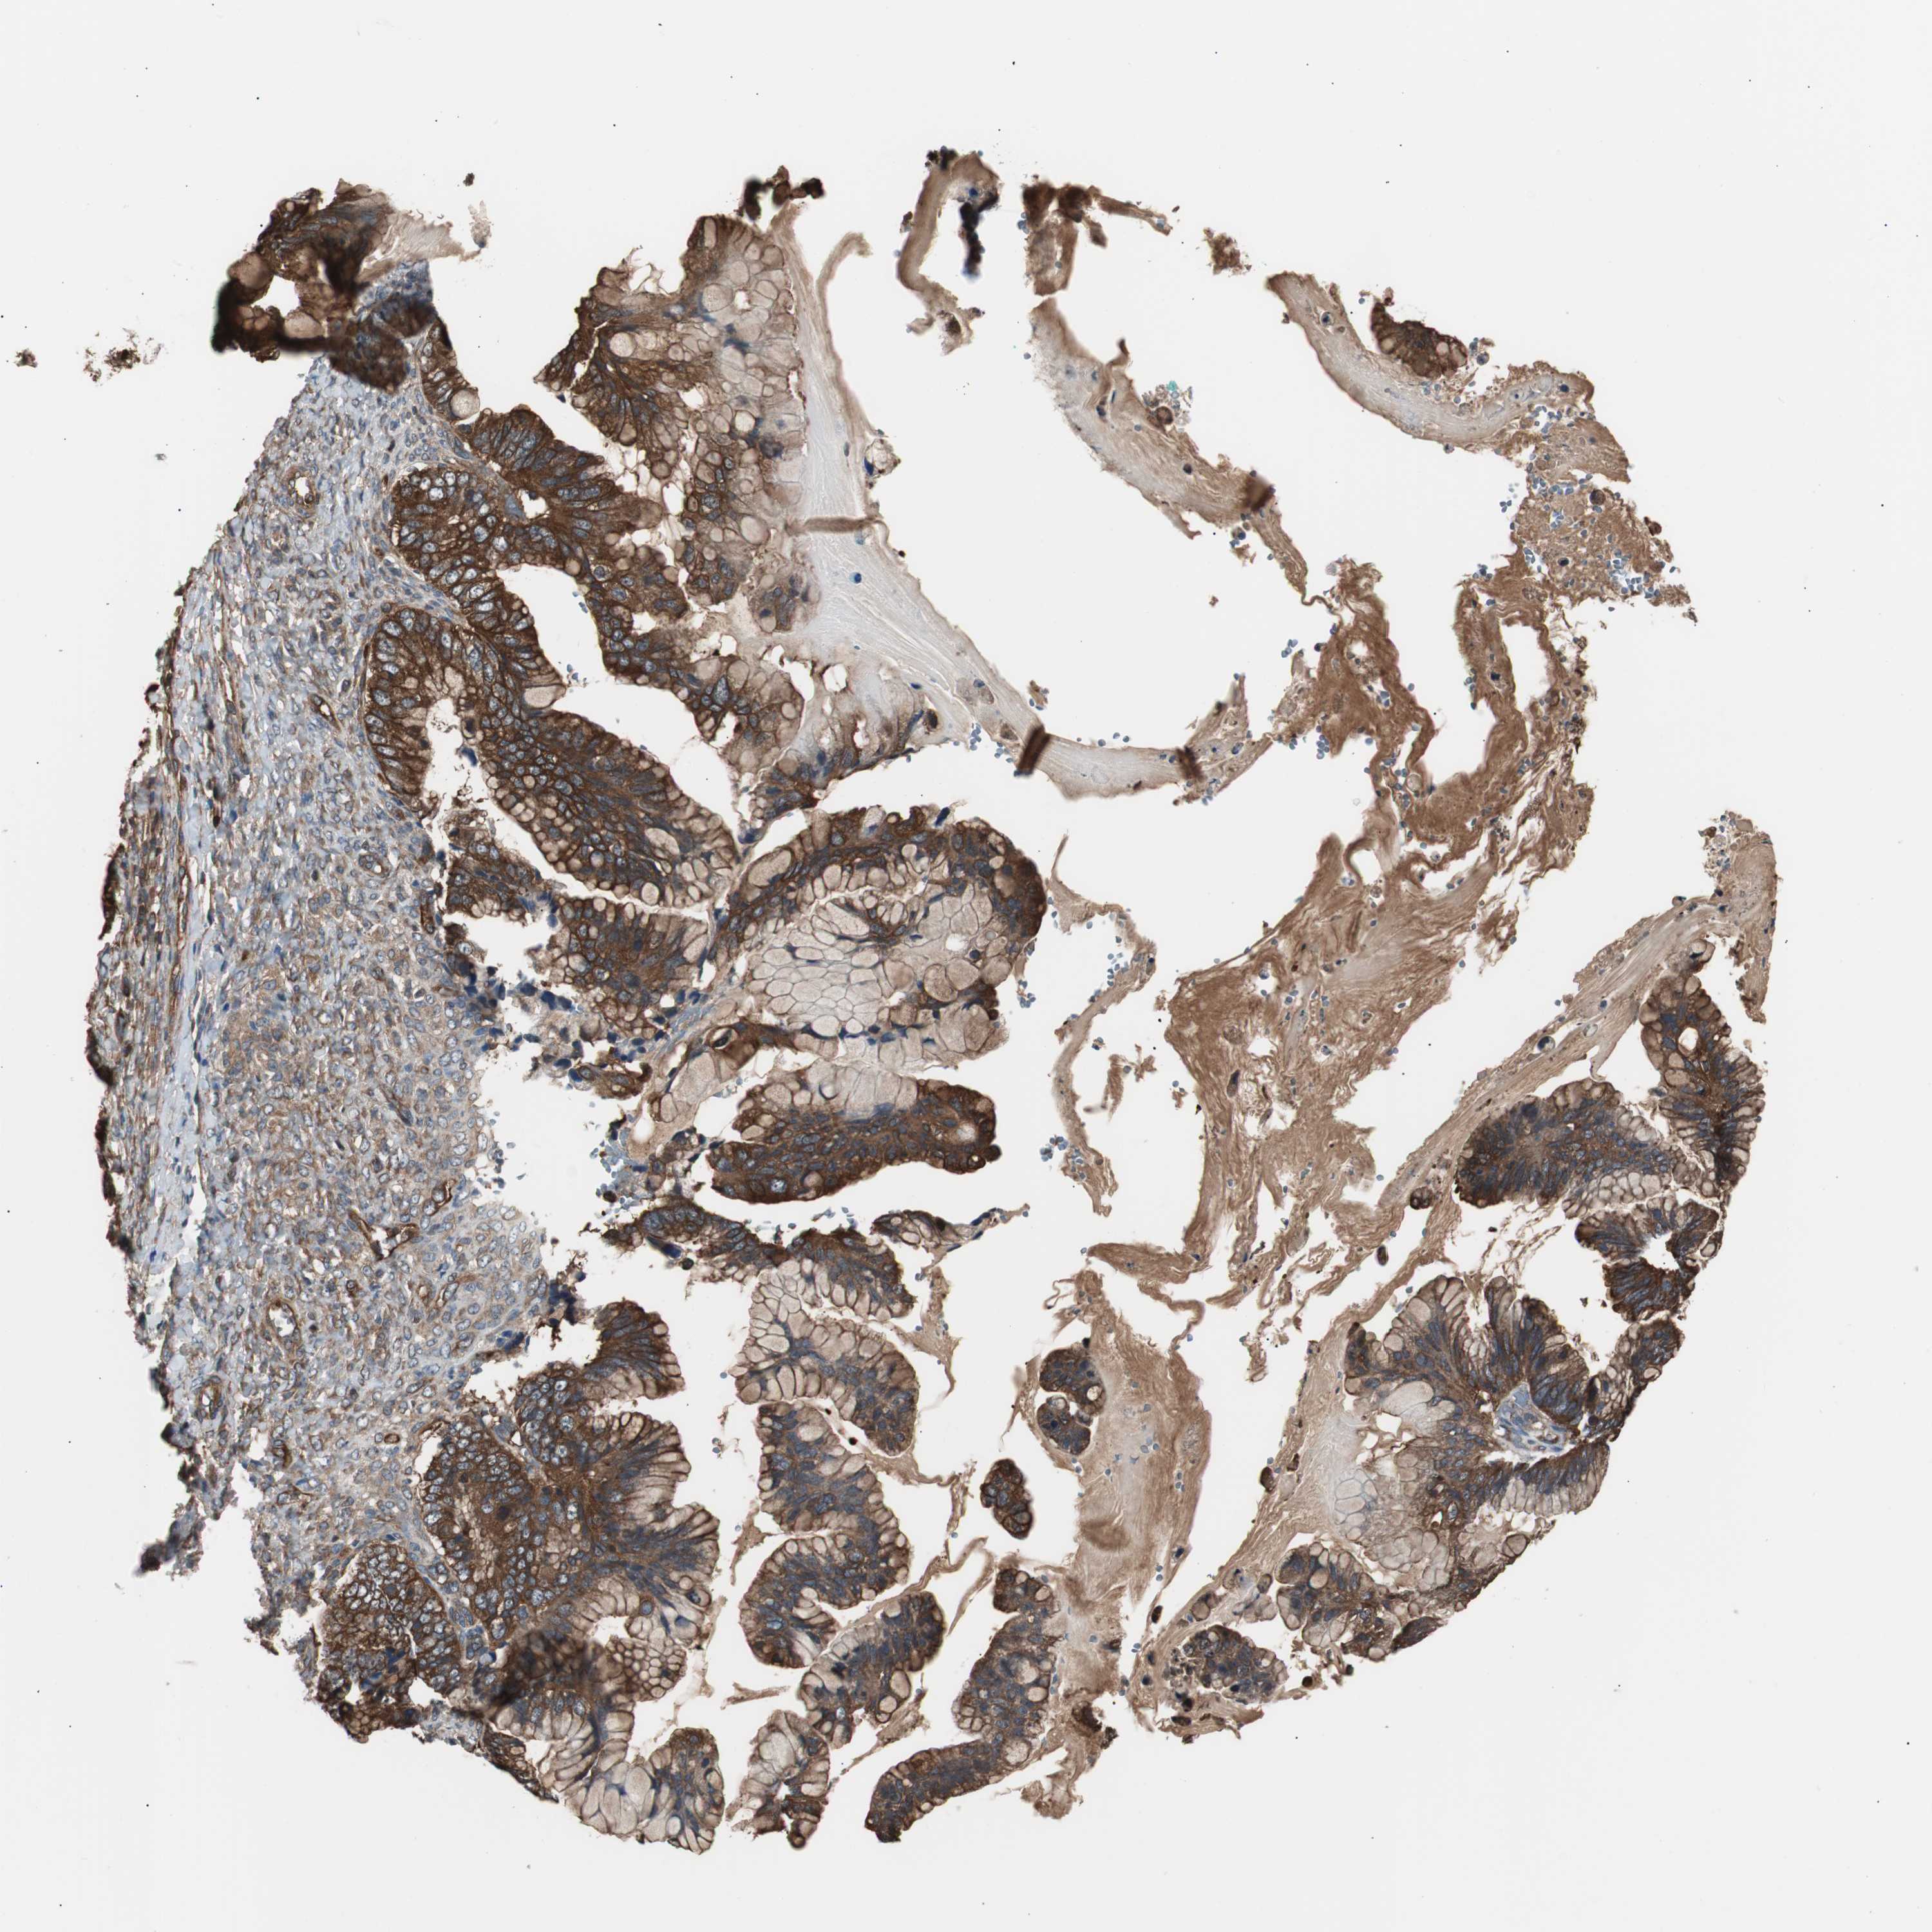

OVARIAN CANCER - Protein expressioni

A mouse-over function shows sample information and annotation data. Click on an image to view it in a full screen mode. Samples can be filtered based on level of antibody staining by selecting one or several of the following categories: high, medium, low and not detected. The assay and annotation is described here.

Note that samples used for immunohistochemistry by the Human Protein Atlas do not correspond to samples in the TCGA dataset.

Antibody stainingi

Antibody staining in the annotated cell types in the current human tissue is reported as not detected, low, medium, or high, based on conventional immunohistochemistry profiling in selected tissues. This score is based on the combination of the staining intensity and fraction of stained cells.

Each image is clickable and will lead to virtual microscopy that enables deeper exploration of all samples and also displays staining intensity scores, fraction scores and subcellular localization as well as patient and tissue information for each sample.

Antibody HPA006872

Staining

High

Medium

Low

Not detected

Intensity

Strong

Moderate

Weak

Negative

Quantity

>75%

75%-25%

<25%

None

Location

Nuclear

Cytoplasmic/membranous

Cytoplasmic/membranous,nuclear

Cystadenocarcinoma, serous, NOS

Carcinoma, endometroid

Carcinoma, NOS

Cystadenocarcinoma, mucinous, NOS